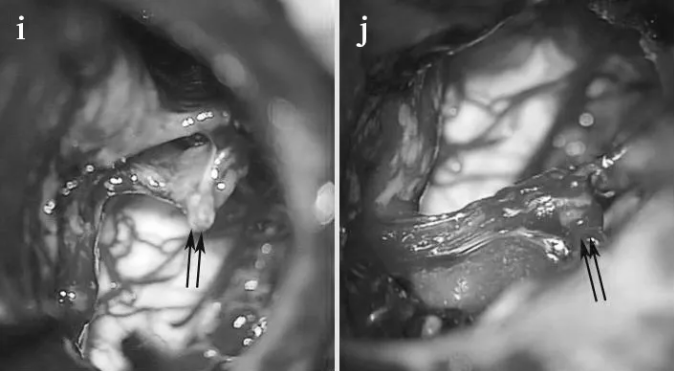

STEP 05:面神经被肿瘤浸润, 在图像上可以看到近端、残端有一些附着的肿瘤(箭头)。